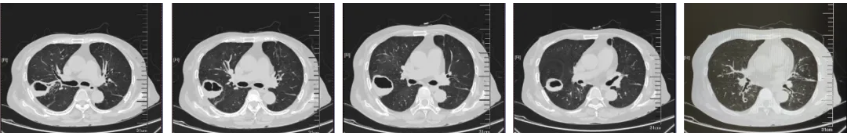

- 胸部CT(图1)(2025-8-15):1、右肺上叶后段空洞性病变(壁厚薄不均,长径约4.9cm,边界尚清,部分边缘稍欠毛糙),双肺多发结节(多发实性、磨玻璃密度结节影,界清,最大者位于右肺下叶背段,长径约1cm,内见空洞),建议CT增强进一步检查。 2、双肺散在炎症、纤维灶;双侧部分支气管轻度扩张;右肺上叶肺大泡。 3、心包部分增厚;主动脉、冠脉多发钙化。 4、腰1椎体楔形压缩。 5、所示双肾形态不规则。

图1.胸部CT(2025-8-15)